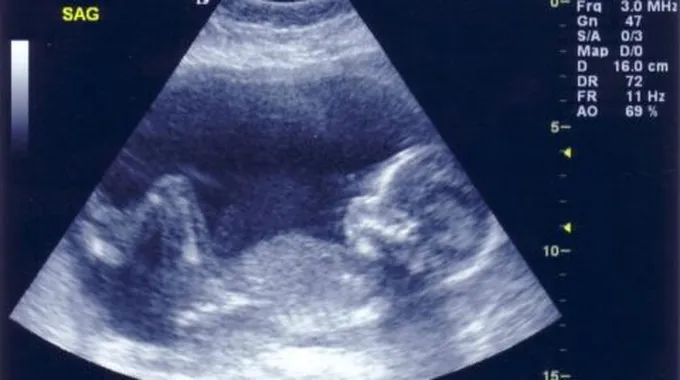

غالباً ما يتم الكشف عن جنس أو نوع الجنين بدجة عالية من الدقة من خلال استخدام جهاز السونار الذي يعتمد على التصوير بالموجات فوق الصوتية (بالإنجليزية: Ultrasound)، ويكون ذلك في العادة ما بين الأسبوعين 18-22 من الحمل، ولكن إن لم يستطع الأطباء المختصون رؤية الأعضاء التناسلية الخاصة بالطفل بشكل صريح وواضح، فربما لا يستطيعون تحديد جنس الطفل، ولن يستطيعوا إخبار الأهل بنوعه بالتأكيد.[3][4]

وعلى الرغم من أنّ تكوين الأعضاء التناسلية للجنين، الفرج للأنثى أو القضيب للذكر، يبدأ بالتطور في مرحلة الأسبوع السادس من مدة الحمل، إلّا أنّ الأجنة الذكور والإناث يبدون متشابهين بشكل تام خلال التصوير بالموجات فوق الصوتية في الثلث الأول (بالإنجليزية: First Trimester) من فترة الحمل وحتى الأسبوع الرابع عشر من الحمل، ولكن وبحلول الأسبوع الثامن عشر قد يكون باستطاعة الطبيب أن يقوم بالكشف عن جنس الجنين، ولكن في حال كان الجنين نائماً بوضعية تجعل الأعضاء التناسلية غير واضحة ومرئية فقد يعيق ذلك قدرة الطبيب على معرفة جنس الجنين؛[3] حيث إنّ الاعتماد الرئيس لتحديد نوع الجنين من خلال الموجات فوق الصوتية الذي يتم في أواخر الطور الثاني من الحمل هو من خلال التصوير المباشر للأعضاء التناسلية الخارجية للجنين.[5] وتجدر الإشارة إلى أنّ التصوير بالموجات فوق الصوتية يُعدّ نوعاً من أنواع الاختبارات التشخيصية غير الجائرة أو الغازية (بالإنجليزية: Non-invasive Diagnostic Tests)، وهذا يدل على عدم وجود أي خطر قد يصيب السيدة الحامل وجنينها بأية أضرار، وقد يقوم الطبيب أو المختص بنصح الأم المستقبلية بالخضوع لإجراء الموجات فوق الصوتية من أجل محاولة تشخيص حالات مرضية معينة قد يكون الجنين مصاباً بها؛ مثل وجود مشاكل في القلب.